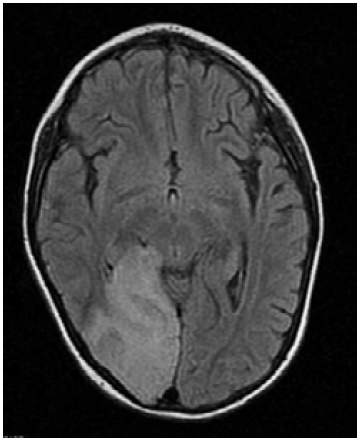

En las neuroimágenes de pacientes con síndrome MELAS se pueden encontrar lesiones cerebrales similares a un infarto cerebral isquémico -especialmente en las regiones posteriores de los lóbulos temporales, parietales y occipitales- pero que superan un territorio vascular; de igual forma, son evidentes las calcificaciones cerebrales en ganglios basales y la atrofia cerebral desproporcionada para la edad del paciente,9 tal como se corroboró en el caso descrito (Figura 2).

Imagen por resonancia magnética cerebral potenciada en T2, corte coronal, en la que se observa lesión isquémica occipital derecha que no se corresponde con ningún territorio vascular.

Figura 2: Imagen por resonancia magnética cerebral potenciada en T2, corte coronal, en la que se observa lesión isquémica occipital derecha que no se corresponde con ningún territorio vascular.

Fuente: Documento obtenido durante la realización del estudio.